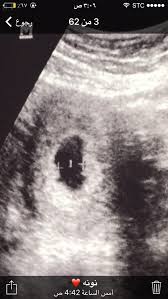

متى يظهر كيس الحمل بالرحم بوابة دوت كوم

متى يظهر كيس الحمل بالرحم بوابة دوت كوم from i.ytimg.com